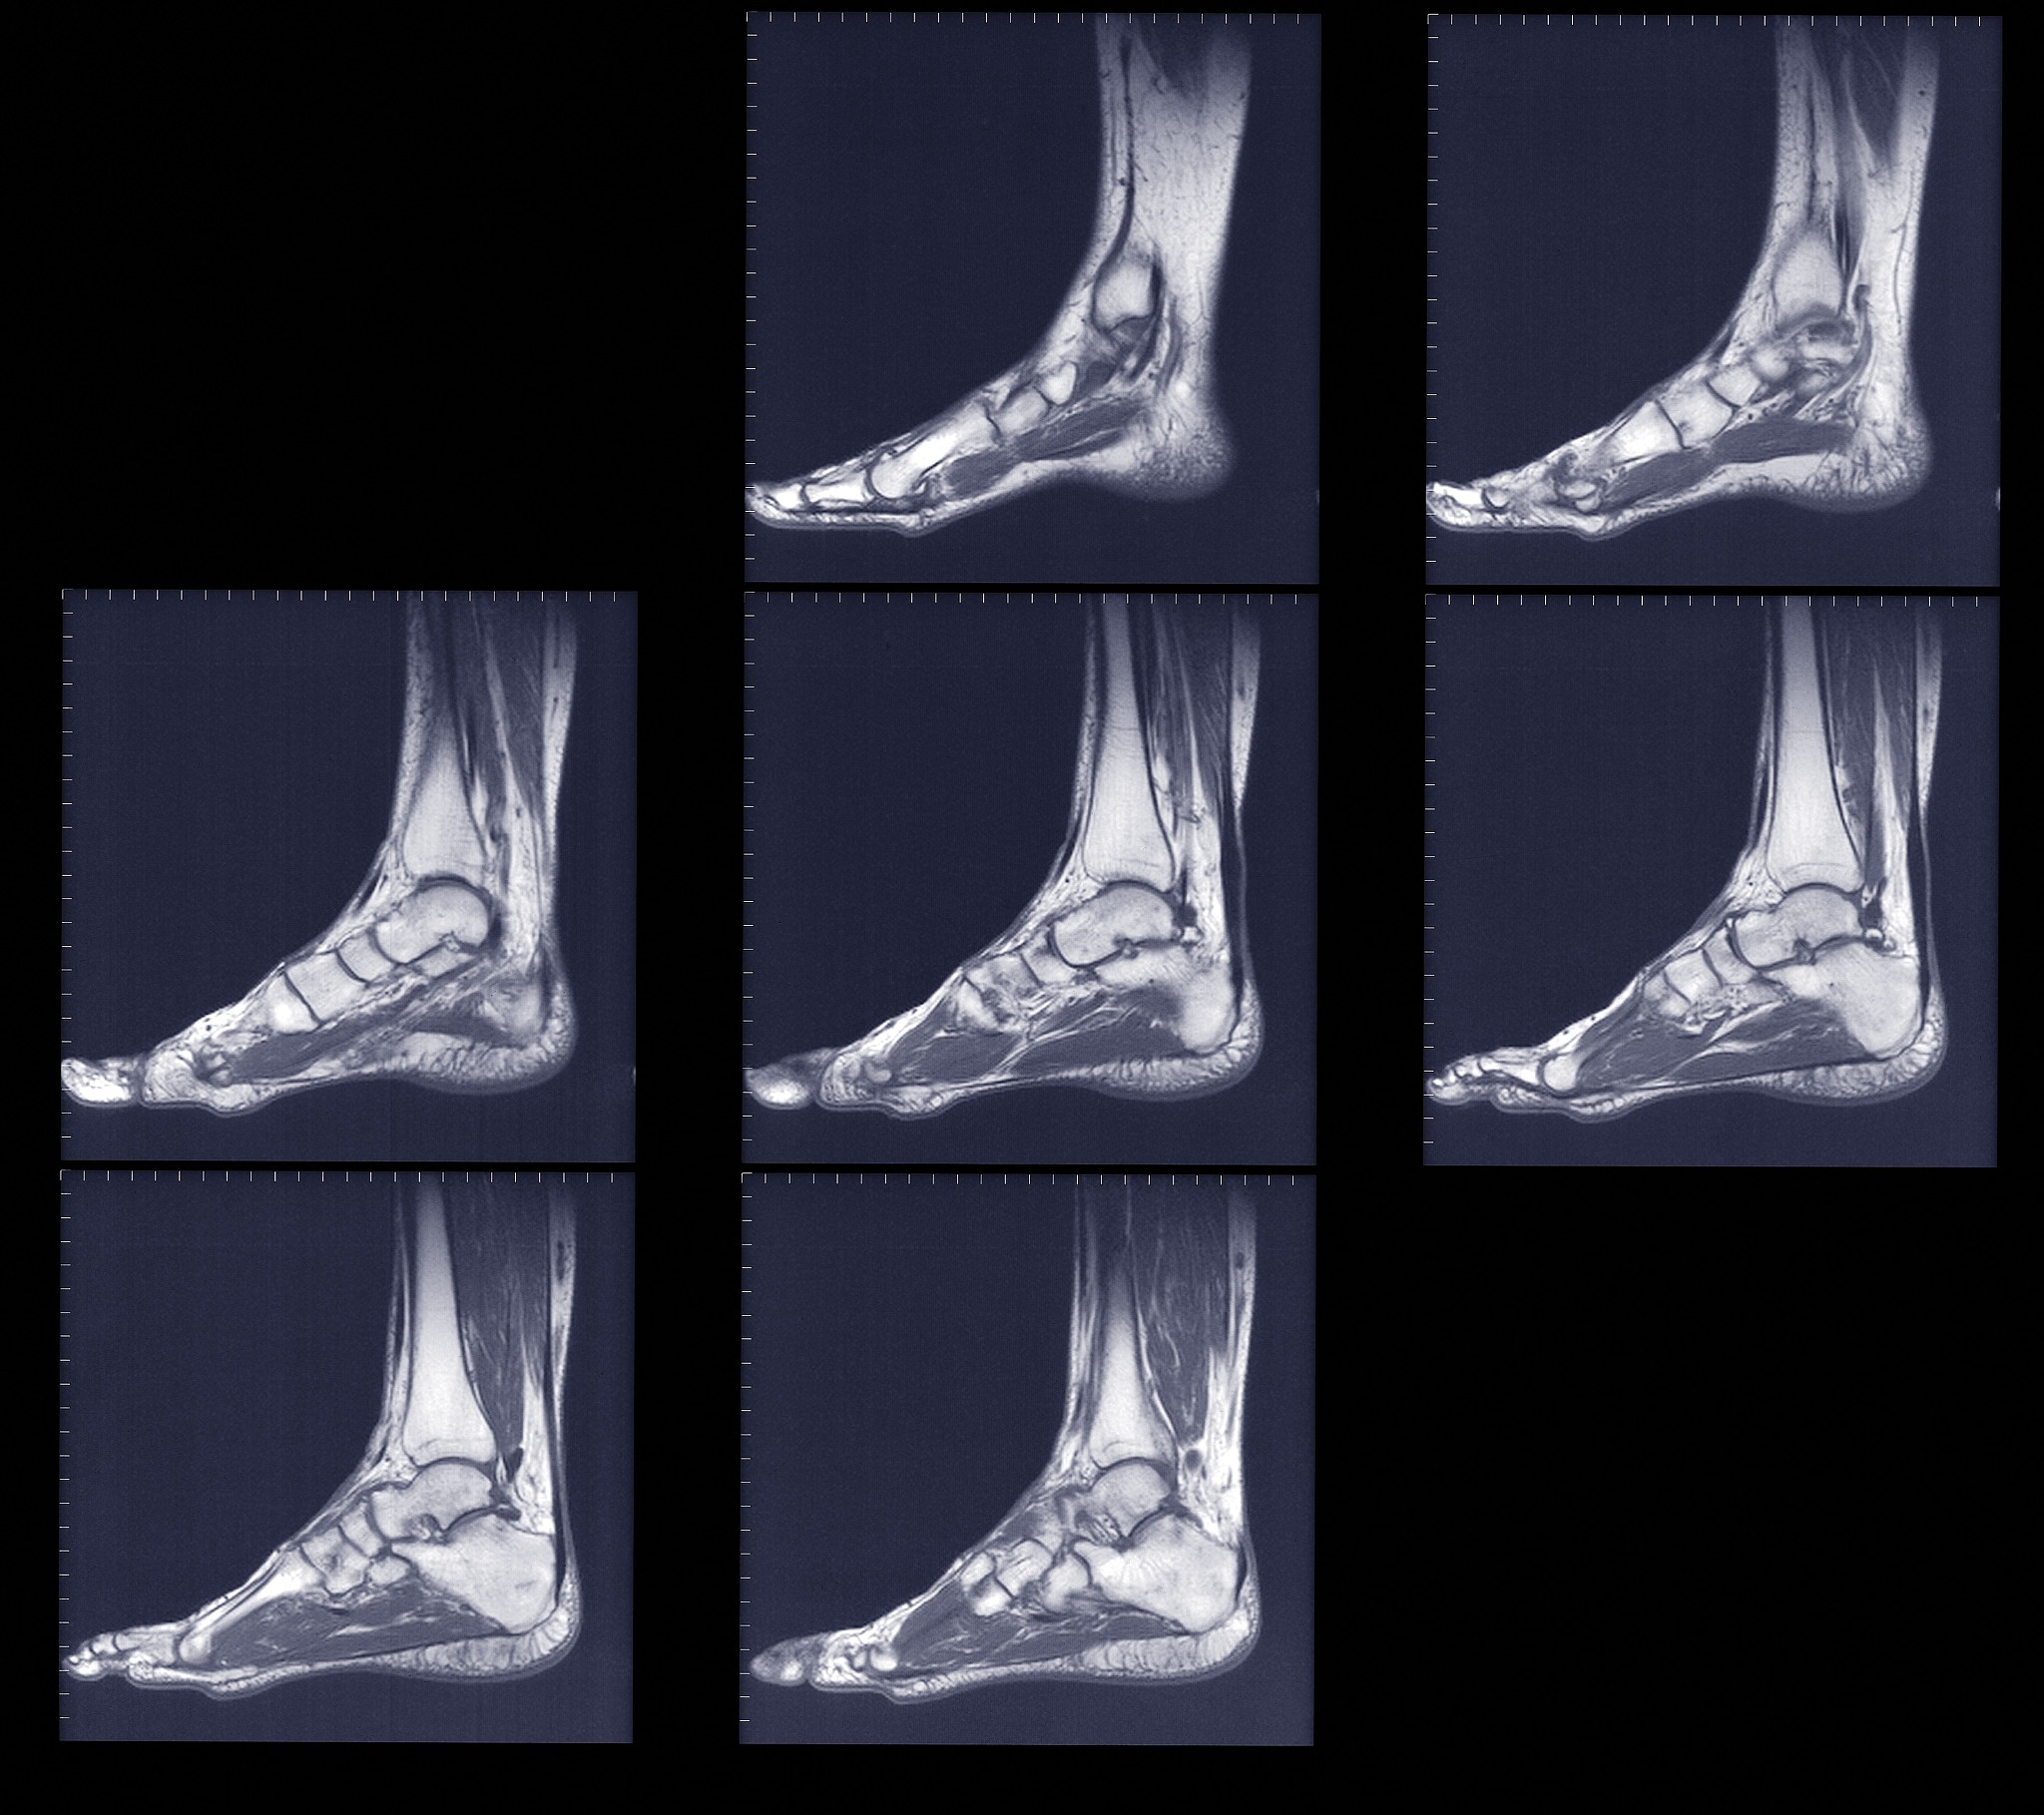

Gould进行了一项改进,他使用了一种伸肌下支持带来加强踝关节外侧副韧带,并重建其稳定性。这种修复技术的特点是伸肌下支持带起源于跟骨外侧面,从而增加了踝关节对抗内翻的稳定性。